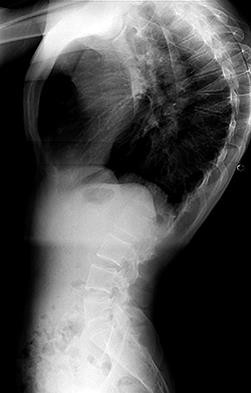

A 25-yo man sustains the injury shown in Figures 29a and 29b as a result of high-speed trauma. Examination reveals diffuse weakness in the lower extremities that is slightly worse on the right side, and decreased rectal tone and sensation. A CT scan is shown in figures 29c and 29d. Definitive treatment of the injury to the spine is delayed because of a severe pulmonary contusion. At 15 days after the injury, the patient’s neurological status remains unchanged. Management should now consist of